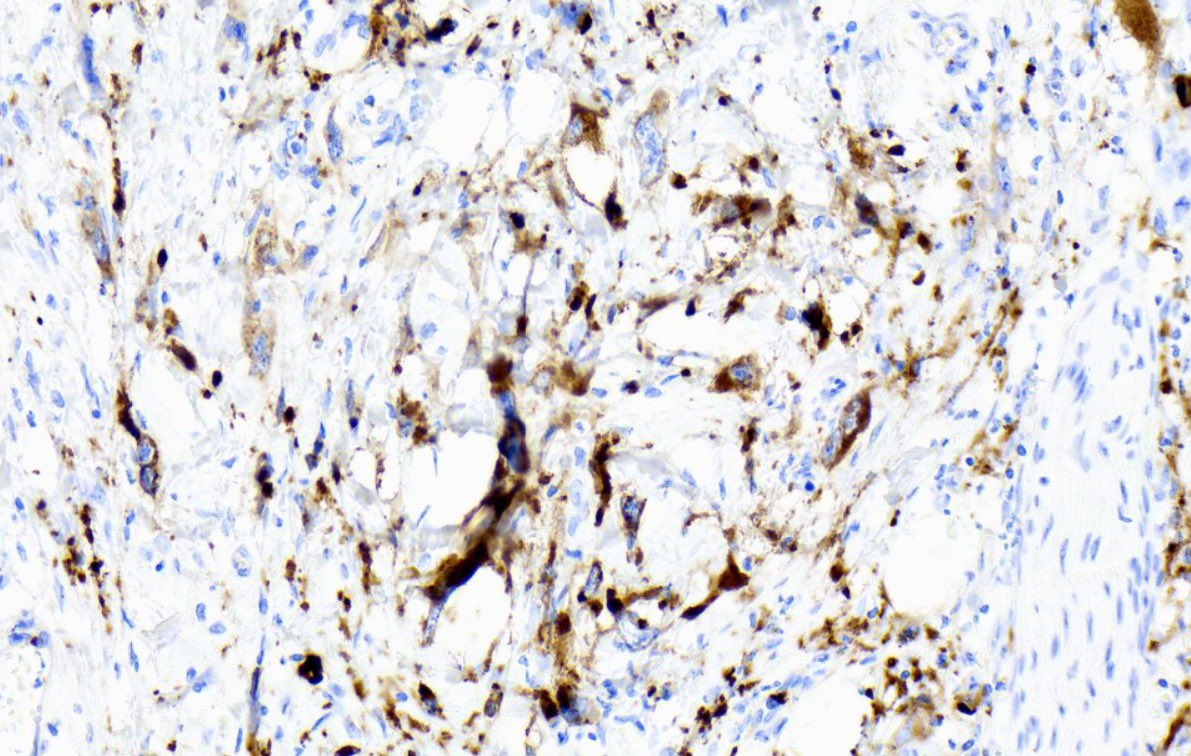

DOG1 negative GIST??? lemme see for myself🔬